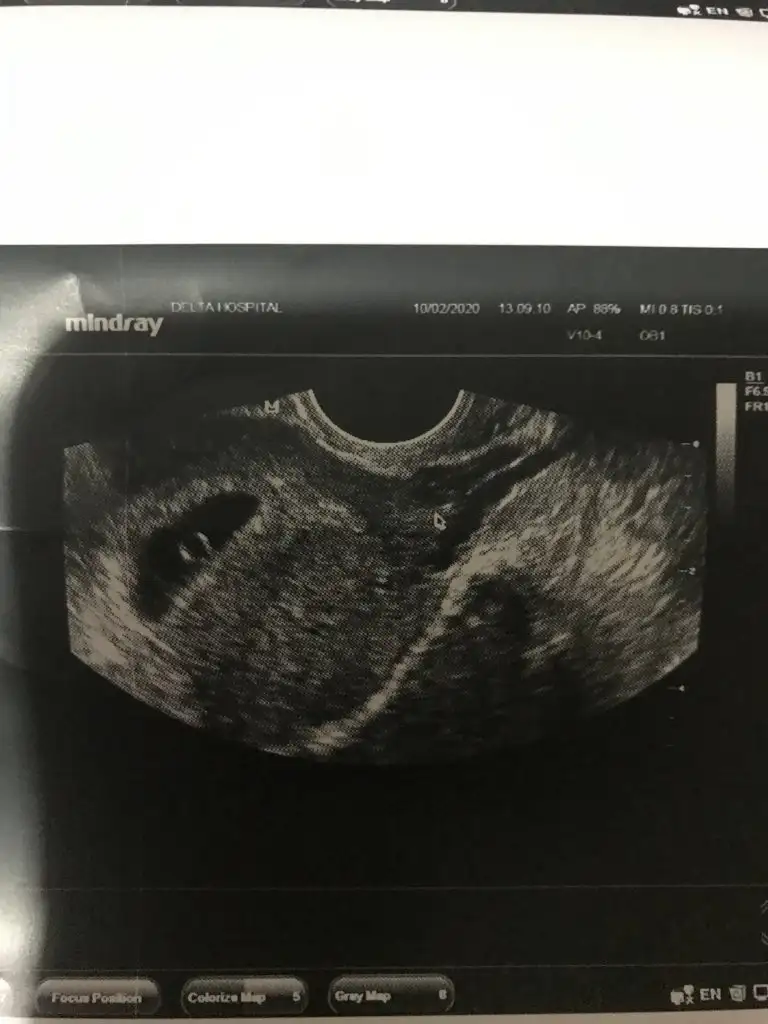

Merhaba cnm dün gittim Bi hastaneye cok güvenmediği m için devlet hastanesinde gittim ikiside kese dısında bsy göremedi Bi 10 mm diğeri 16 mm dediler kese için bnimde canm sıkıldı 6 haftalık bebek artıkgözükmesi gerekir Di cunkü bgn özel muayenehanesi olan Baska Bi doktora gittim hem bebeği gördüm hem kalp atısını duyduk cok garip walla 2 gündür kafam corba oldu bu nasıl iş anlamadım 350 TL muayene ücreti verince hersey görülüyor sanırımTamam canım güzel haberler ile gel inşallah